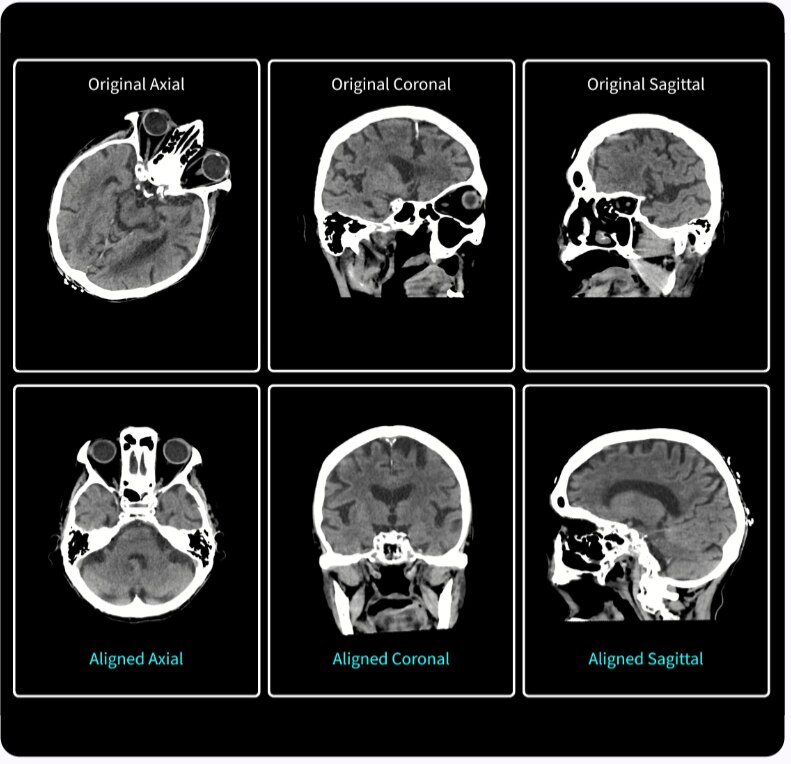

SIGNA™ Champion offre un design modulare con opzioni software e hardware pronte per soddisfare le priorità cliniche. Include strumenti di base e avanzati e soluzioni per la qualità delle immagini come AIR™ Recon DL e Sonic DL™. Queste applicazioni consentono non solo di ottimizzare i casi di routine, ma anche di operare in altri campi specifici come neurologia, apparato muscolo-scheletrico, cardiologia e oncologia. E non è tutto. SIGNA™ Champion è in grado di offrire configurazioni a 32, 48 e 64 canali per garantire la massima flessibilità e semplificare la configurazione delle bobine sulla base delle diverse anatomie.

AIR™ Recon DL

AIR™ Recon DL potenzia le funzionalità della tua RM offrendo una qualità dell'immagine superiore con tempi di scansione ridotti.